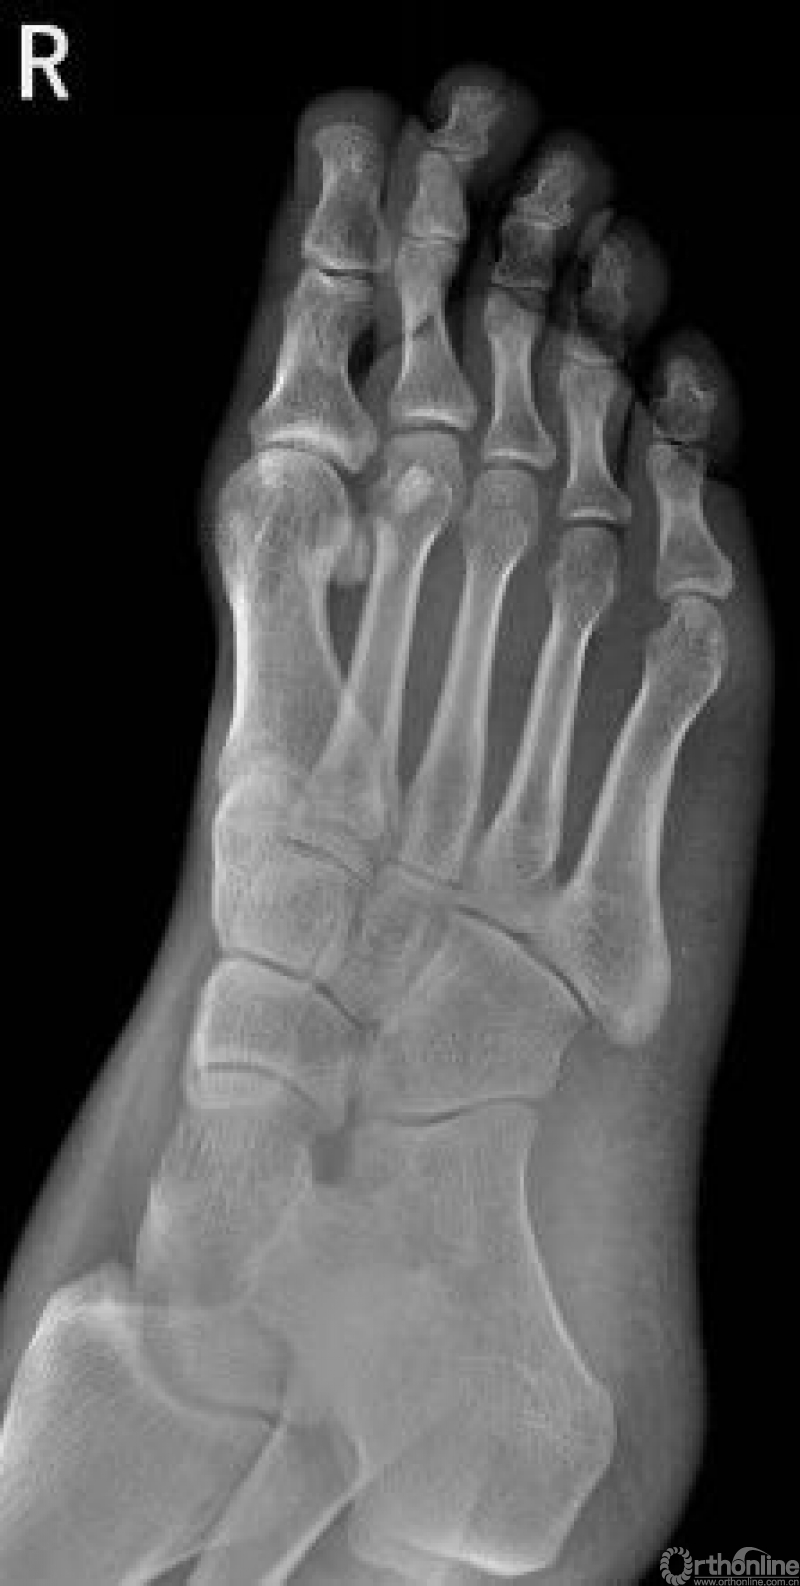

足

右足斜位示 右侧跟骨前部见骨折透亮线。右跟骨前部骨折

左侧跟骨见骨折透亮线,后缘骨皮质连续中断。左侧跟骨骨折

右足第5跖骨基底部见骨折线,断处稍分离移位。右足第5跖骨基底部骨折

Warmreminder: 儿童时期足第5跖骨处有骨骺存在,骨骺线易与骨折线混淆,小妙招给你,骨骺线的长轴一般是与第5跖骨长轴平行,而第5跖骨多是横行骨折,换言之骨折线与第五跖骨长轴垂直。